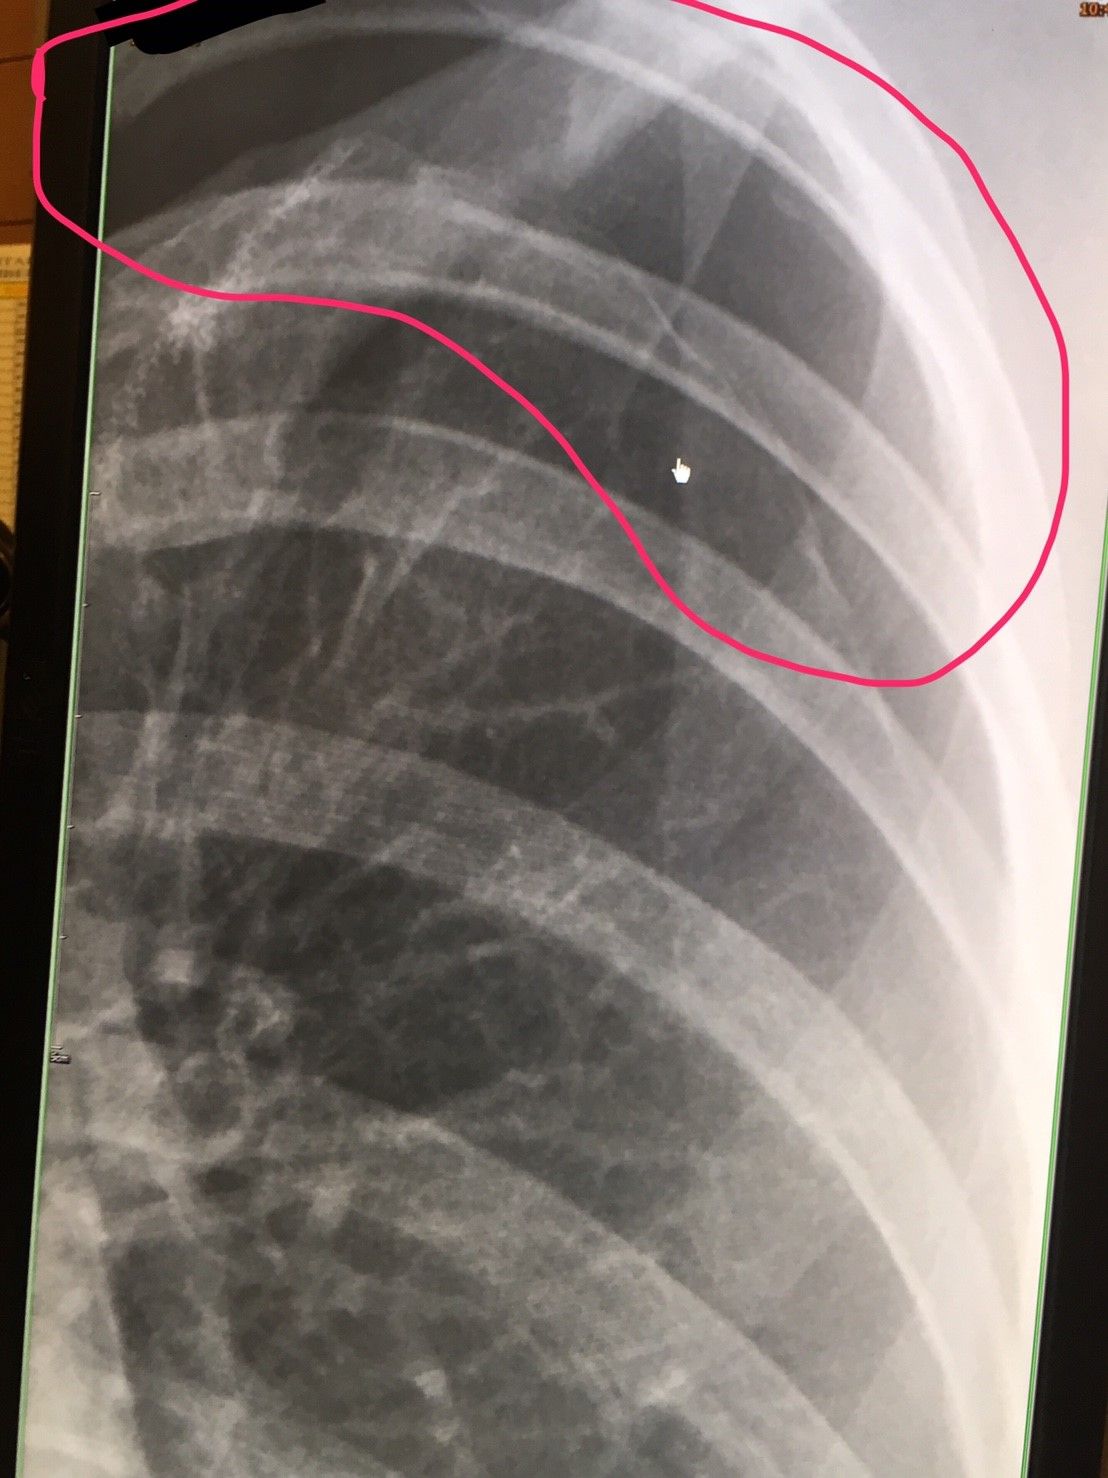

ภาพตัวอย่างตอนเป็นปอดรั่ว

อันนี้ภาพรั่วครั้งที่ 3 จะให้ดูว่าเส้นสีขาวๆที่เห็นก็คืออากาศที่เราสูดเข้าไปมันจะยาวไปทั่วปอด (ในวงกลมดำ) แต่วงกลมแดงมันจะเป็นสีดำปี๋ซึ่งหมายความว่าไม่มีอากาศไปถึง

จะเห็นเส้นปอดเลยว่ามีช่วงถมดำเล็กๆด้านบนซึ่งนั่นคืออากาศที่รั่ว